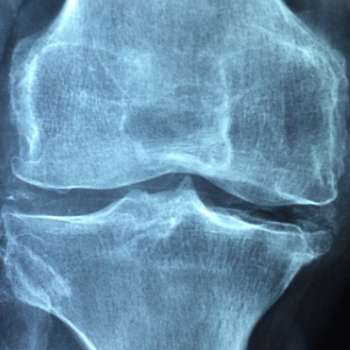

무릎에 물이차는 원인 1. 관절염 (Arthritis)

- 관절염은 무릎 관절에서 발생하는 염증으로, 주로 류머티즘 관절염, 골관절염, 혹은 강직성 척추염과 같은 다양한 형태가 있습니다. 무릎 관절 내의 연조직을 공격하여 염증 반응을 유발하며, 이로 인해 통증과 함께 물이 찰 수 있는 상황이 발생할 수 있습니다.

무릎에 물이차는 원인 3. 퇴행성 관절 질환

- 퇴행성 관절 질환은 무릎 관절의 연골이 시간이 지남에 따라 닳아지고 손상되는 상태를 포함합니다. 주로 고령자에서 발생하며, 연골의 감소로 인해 무릎 관절 내에 물이 찰 수 있는 조건이 형성됩니다. 이는 관절을 보호하는 기능을 약화시키고 물이 축적되게 합니다.

무릎에 물이차는 원인 4. 연골 손상

- 무릎의 연골은 관절을 부드럽게 움직이게 하고 충격을 흡수하는 역할을 합니다. 그러나 부상, 과도한 스포츠 활동, 나이 등의 요인으로 인해 연골이 손상될 수 있습니다. 연골 손상으로 인해 관절에서 마찰이 증가하면서 염증이 발생하고, 이로 인해 물이 찰 수 있습니다.